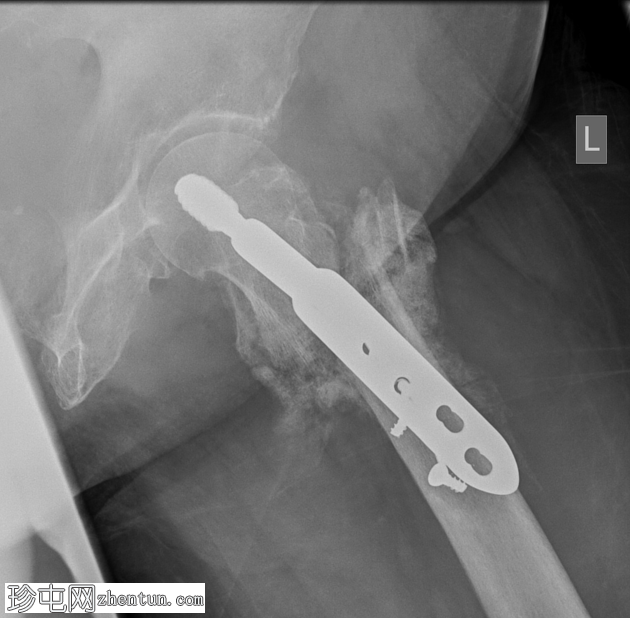

X线片

侧位片

最下方三枚螺钉发生骨折,螺钉头移位。远端钢板松动。骨膜广泛钙化,股骨颈骨折仍清晰可见。

这是一个动力髋螺钉内固定失败的案例。该患者的具体原因尚不明确,但通常包括:骨质疏松、骨折类型/粉碎程度以及手术技术问题。